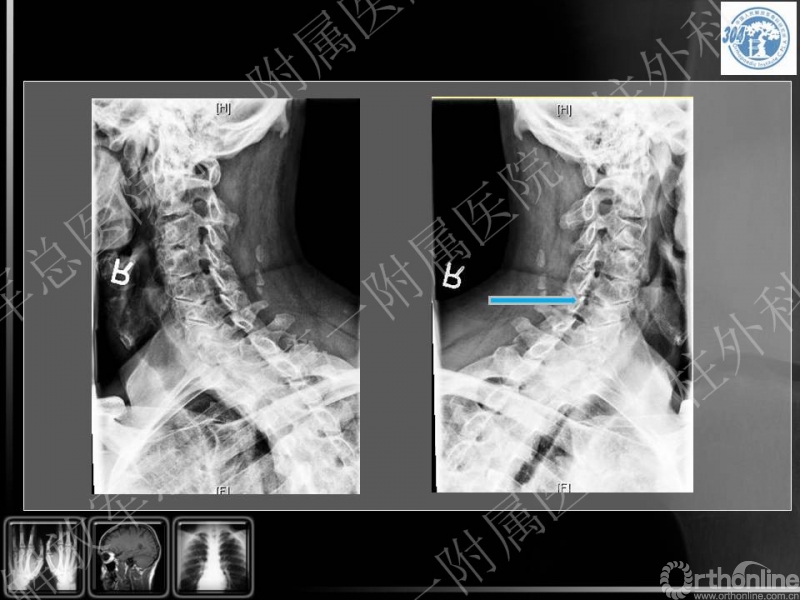

72岁 男性,既往体健,无严重基础疾病,6年前腰椎手术史

右侧前臂外侧及右拇指麻木疼痛,影响睡眠,超过3月不缓解,双手协调控制差

四肢关键肌肌力基本正常,肌张力增高,步态改变

腱反射亢进,双侧Hoffman征(+)

手术选择,前路,后路,前后联合?

手术节段和范围?

神经根出口狭窄是否需要处理?

本病例的特点为患者既往有颈椎病的基础,近期出现右上肢疼痛、麻木症状,老年,专家讨论要点主要集中在患者手术前后路选择,节段选择及手术时机等。

李放教授:

患者缺乏X光片颈椎管椎管比值的测量,但基本可见患者有明确的发育性颈椎管狭窄,又有颈椎退变增生的病理基础,核磁见多节段的颈脊髓压迫,近期出现右上肢疼痛麻木症状,体格检查脊髓和单一神经根损害表现,为混合型颈椎病(脊髓型/神经根型)。可考虑行颈椎管扩大成形术,包括单开门/双开门等方式,结合单一神经管切开减压,可达到全面的治疗效果。

蒋毅主任:

同意李放教授的观点,提出部分学者甚至认为单开门术中常规切开颈4-5神经根管,防止出现颈5神经根病。

党耕町教授:

同意以上观点,对郭继东副主任医师采取的短节段后路开门的治疗方案予以肯定。同时他提出根据老年患者对生活质量的需求,其可能仅想解除短期内的新发的上肢麻木症状,仅行责任节段的神经根管切开术。